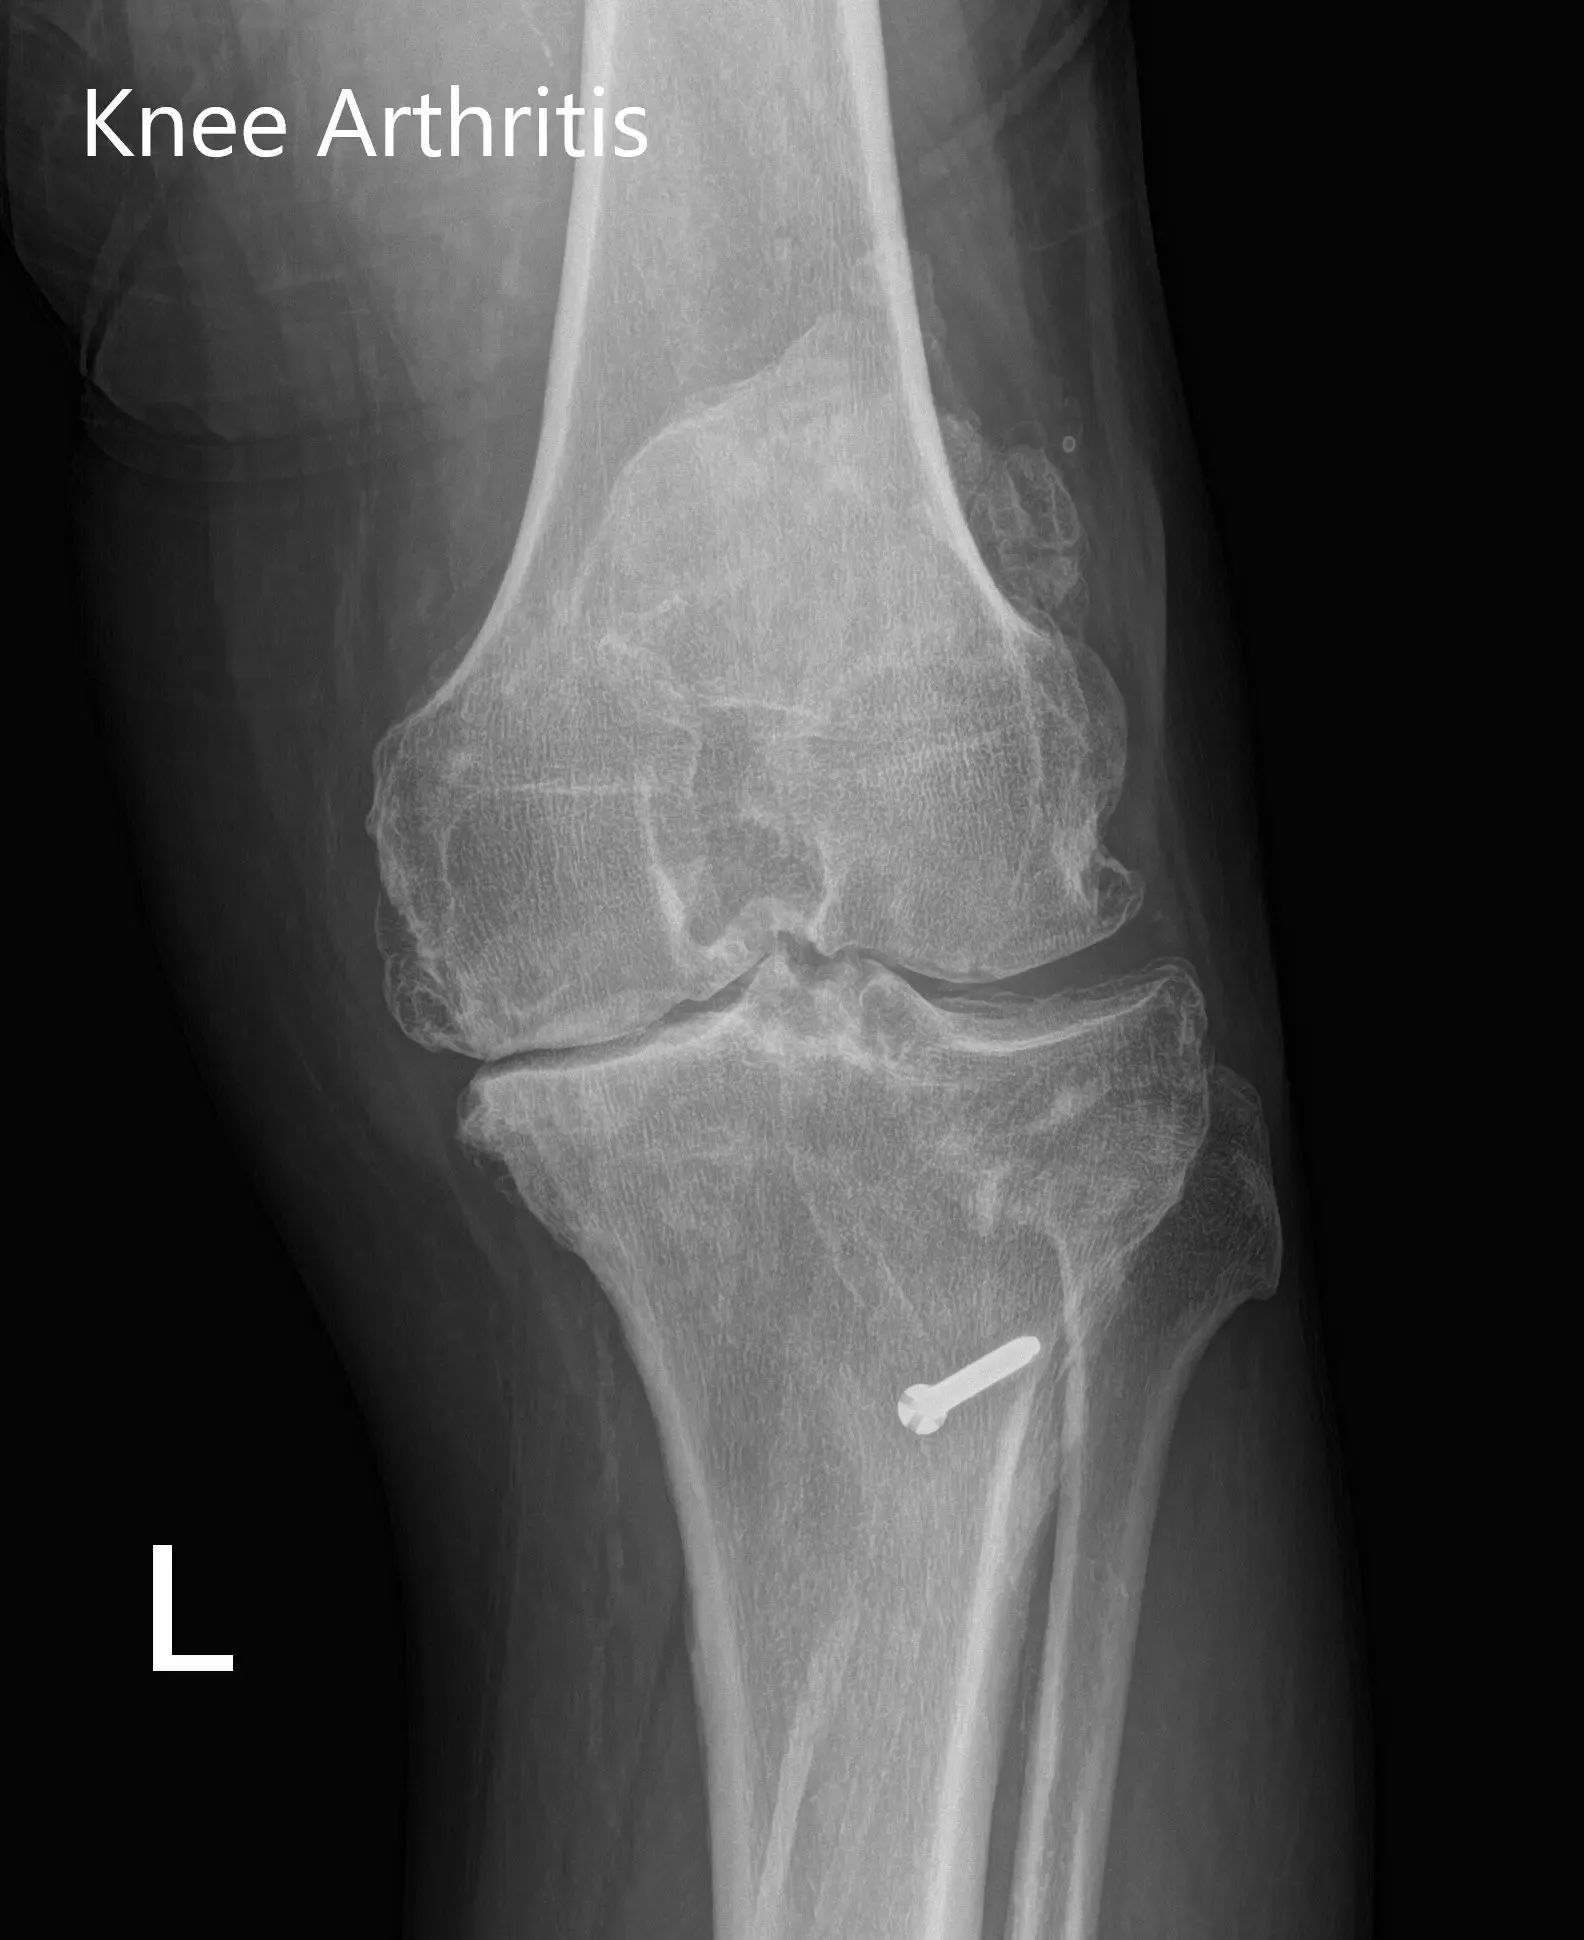

Sus estudios de imagen revelaron osteoartritis tricompartimental de la rodilla izquierda con un perno retenido (perno) en la tibia proximal izquierda. Tras evaluar sus condiciones médicas y examinarse físicamente, se consideró candidata para una prótesis de rodilla personalizada. Se le recomendó someterse solo al lado izquierdo debido a los antecedentes previos de infracciones miocárdicas y luego proceder a la rodilla derecha.

Radiografía preoperatoria de la rodilla izquierda que mostró visión AP y lateral con cambios osteoartríticos degenerativos y hardware retenido en la tibia proximal.